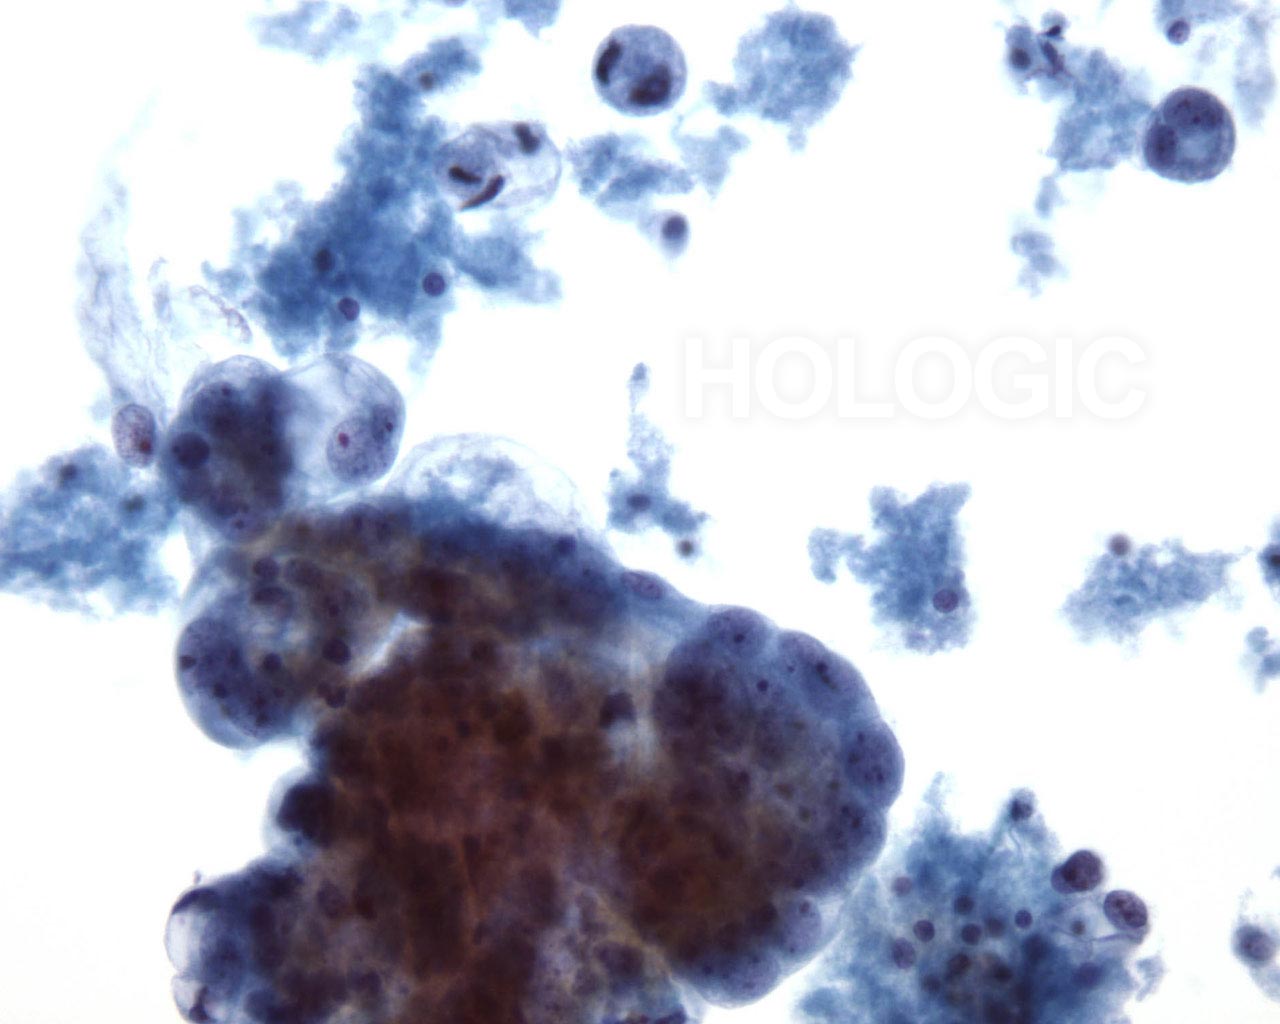

Abbildungen 43-45: Pleuraerguss: Serös-papilläres Adenokarzinom des Ovars.

Zellen des serös-papillären Adenokarzinoms des Ovars in einem Pleuraerguss können als diskontinuierliche Zellpopulation vorliegen. Die Zell- und Zellkerngrößen sind unterschiedlich. Merkmale sind eine erhöhte Kern-Plasma-Relation und zytoplasmische Vakuolen. Die Zellen können einzeln oder in kleinen azinösen Gruppen auftreten.